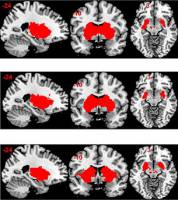

Biowissenschaften - 23.12.2015

Das Zwischenhirn leitet nicht nur - wie bislang angenommen - optische Reize an das Grosshirn weiter, sondern sendet auch Zusatzinformationen. Diese sind essenziell, um das Gesehene richtig einordnen und angemessen reagieren zu können. Prof. Sonja Hofer und ihr Forschungsteam am Biozentrum der Universität Basel erforschen die Verarbeitung von Sehreizen im Gehirn und wie Kontextinformationen übermittelt werden.

Gesundheit - 25.06.2015

Zielgruppeneinstiege Navigation Mitarbeitende weitere Informationen Alumni weitere Informationen Medien weitere Informationen Forschende weitere Informationen Dozierende weitere Informationen Doktorierende weitere Informationen Studieninteressierte weitere Informationen Studierende weitere Informationen Studierende aus dem Ausland weitere Informationen Fruchtzucker sättigt nicht nur weniger, sondern stimuliert auch das Belohnungssystem im Gehirn in geringerem Mass als Traubenzucker.